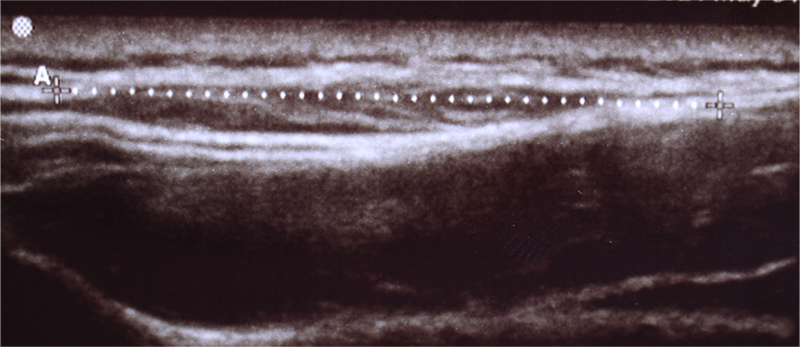

手術の前にエコー検査などの画像検査を行い、位置(深さ)を同定します。 深部に存在するものや、大事な血管や神経などの組織が近くに存在する部位の腫瘍や、症状や臨床経過から悪性腫瘍などの可能性も考慮する必要があるものはMRIなどの検査も行います。今回の症例では画像検査の結果、背部の皮下・軟部腫瘍を認めました。

他院整形外科でMRI検査にて左大腿の大腿直筋内に脂肪腫様の軟部腫瘍を指摘され経過観察となっていました。当院での超音波検査でも筋肉内に腫瘍を認めました。